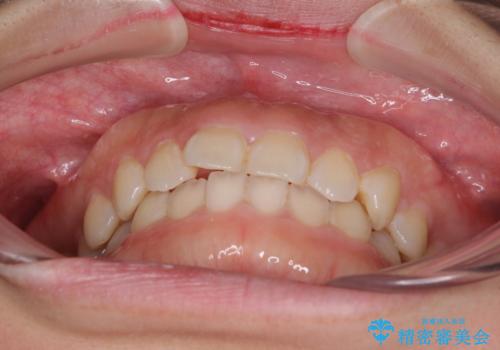

- 前歯のデコボコを治したいとのことで来院された患者様です。

上下顎ともに歯列全体の側方拡大とIPR(歯と歯の間を削る)によってデコボコが解消するように設計し、インビザラインにより治療を行うこととしました。